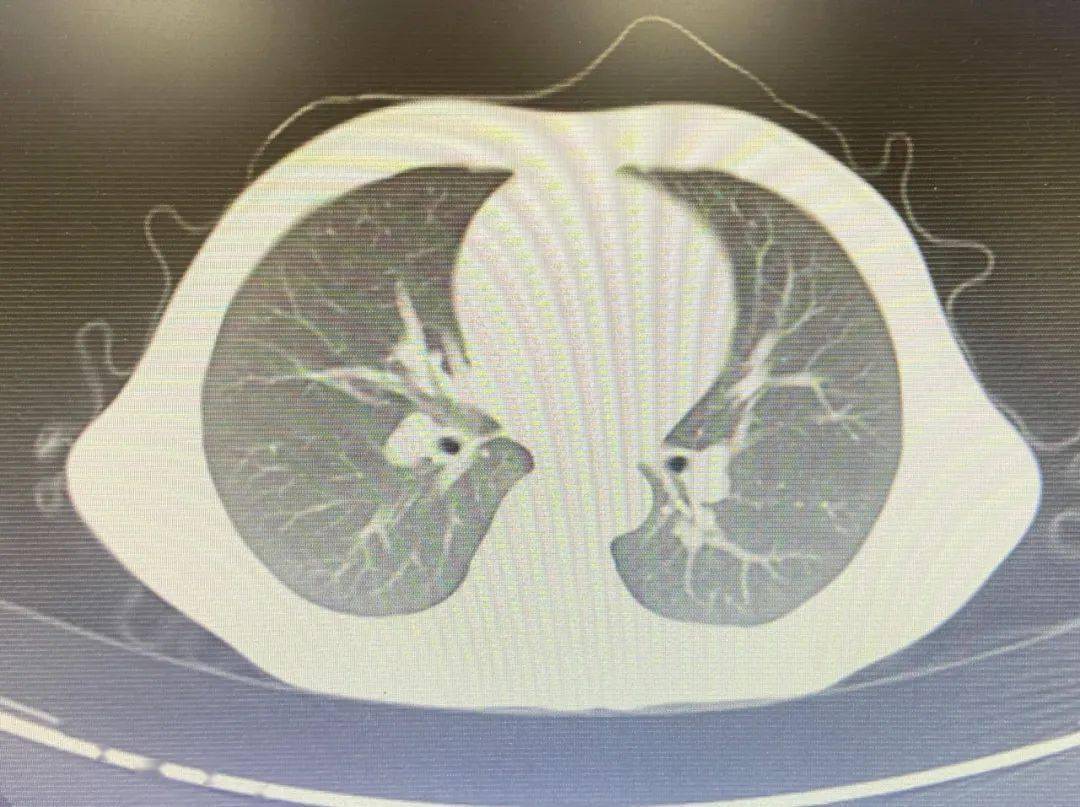

9个月的宝宝反复肺炎3个月,ct提示支气管异物纤维支气管镜下见异物

支气管镜检查:双肺支气管各段粘膜充血,肿胀,可见纵行皱褶,支气管灌